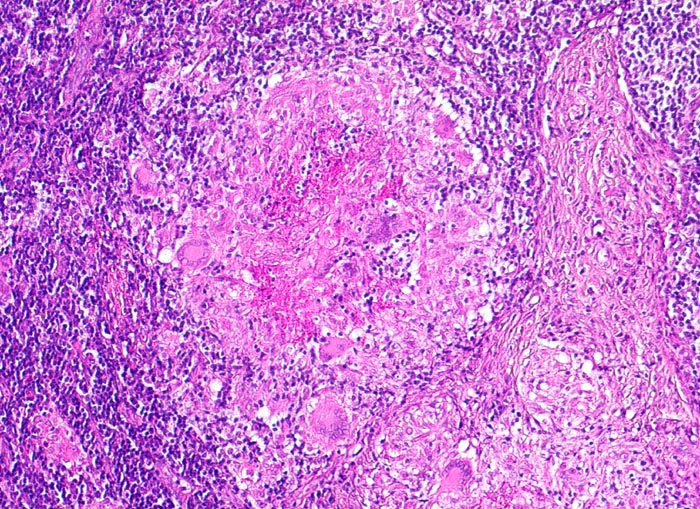

PathoPic ID 4010 - Lymphknotentuberkulose: verkäsendes Granulom und Vernarbung

Lymphknotentuberkulose: verkäsendes Granulom und Vernarbung

Links im Bild ein zentral verkäsendes Granulom mit Langhans Riesenzellen. Rechts davon Vermehrung von Kollagenfasern.

Konglomerattumor am Hals mit Fistelbildung bei Patient aus Zimbabwe.

Tuberkulosegranulome können durch zunehmende Produktion von Kollagenfasern vernarben. Die Nekroseareale können verkalken.